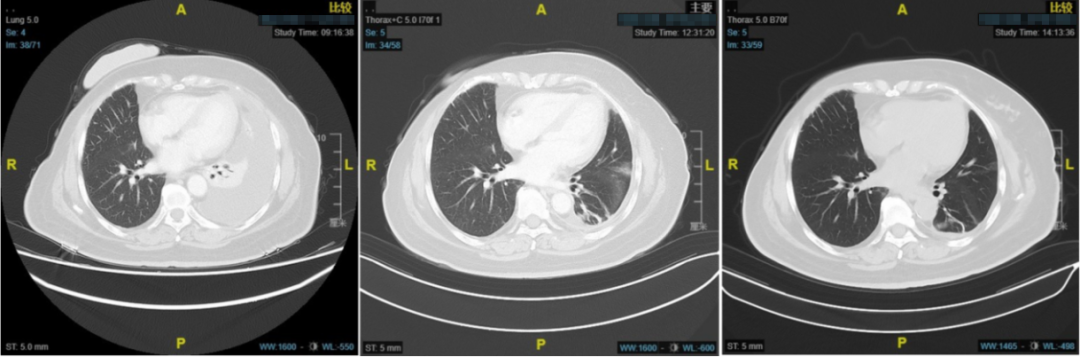

一线治疗不良事件:第1周期化疗后出现4度粒缺,伴发热39.3℃,胸部CT示左肺炎(图1),予以抗炎治疗后恢复;第2周期化疗减量20%;纳差1度,乏力1度。

图1.一线化疗1周期后胸部CT示左肺炎